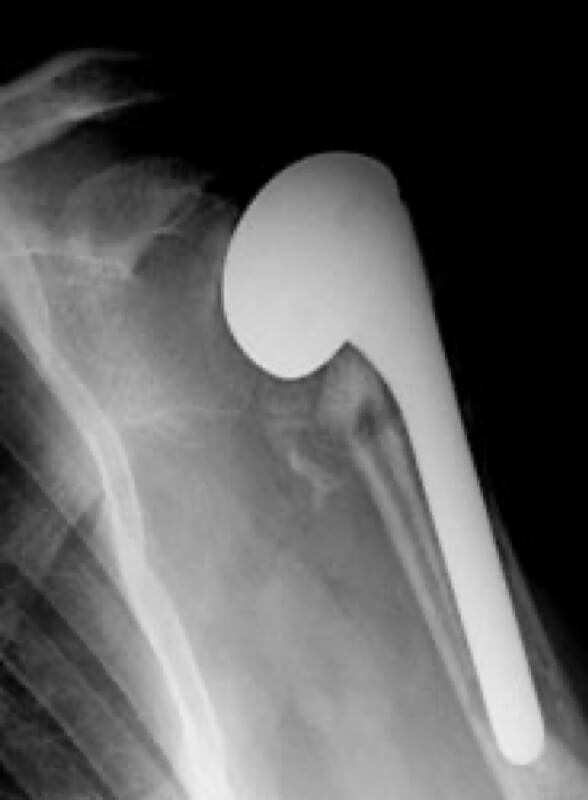

American Shoulder and Elbow Surgeons > Stryker/Wright/Tornier, Solar

Stryker/Wright/Tornier, Solar